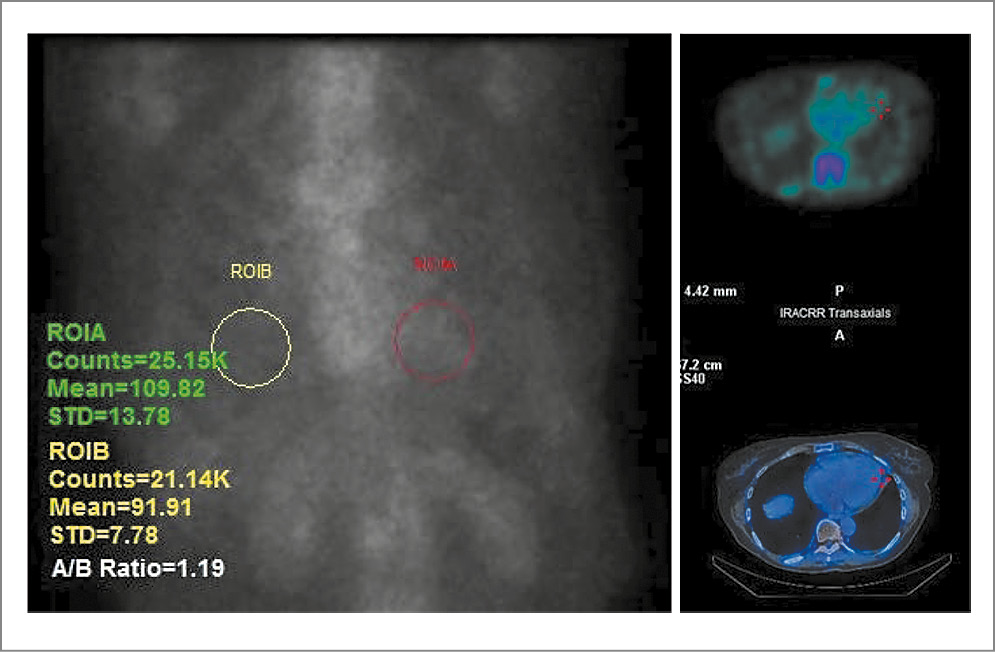

Учитывая данные инструментальных и лабораторных методов исследования, приняли решение о проведении сцинтиграфии миокарда с 99mTc-пирофосфатом (торговое наименование Пирфотех, 99mTc) для исключения ATTR-амилоидоза. Через 3 ч после внутривенного введения 740 МБк радиофармпрепарата (РФП) на гибридном томографе GE NM\CT 860 провели планарное сканирование и однофотонную эмиссионную компьютерную томографию (ОФЭКТ-КТ) органов грудной клетки без контрастирования (рис. 5).

Рис. 5. Планарное сканирование и ОФЭКТ-КТ органов грудной клетки без контрастирования.

По суммарным результатам радионуклидного обследования специфических признаков ATTR-амилоидоза не выявлено, так как индекс накопления РФП в миокарде относительно контралатеральной стороны в правом легком был равен 1,19 (не превысил диагностический рубеж 1,3). При этом накопление РФП локализовалось преимущественно в пуле крови, а не в толще миокарда, что позволило с высокой вероятностью исключить ATTR-амилоидную кардиомиопатию.